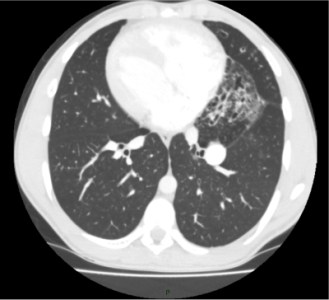

Chest infections are common, especially after a cold or flu during autumn and winter.Hi, Normally if there is an infection in the chest there will be yellow or green sputum when your wee one coughs up. However, its not always possible to get them to About natural common cough remedies and symptoms, side-effects, respiratory phlegm, allergies and congestion.Lung cancer does not usually causes any symptoms in the early stages of the disease. Once warning signs become apparent, the cancer may have progressed.When a person says 'right or left side of chest hurts when I cough', the causes may vary from common cold to severe lung problems such as bronchitis or pneumonia.Chest infection is a disease that influences your lungs, either in the bigger aviation routes (bronchitis) or in comparatively small air sacs (pneumonia).Chest Cold Information Including Symptoms, Diagnosis, Treatment, Causes, Videos, Forums, and Local Community Support.Visit oure website - http://chiropractorfortworth.org - Chest Infection Symptoms. Chest infection is quite common among both adults as well as small Most children develop cough after a cold. Most coughs are caused by viruses and so antibiotics are of least help. A cold is often followed by chest infections.Chest Burning with Cough. Chest pain accompanied by burning and coughing can be caused due to a number of ailments, both, curable and chronic. It therefore becomes